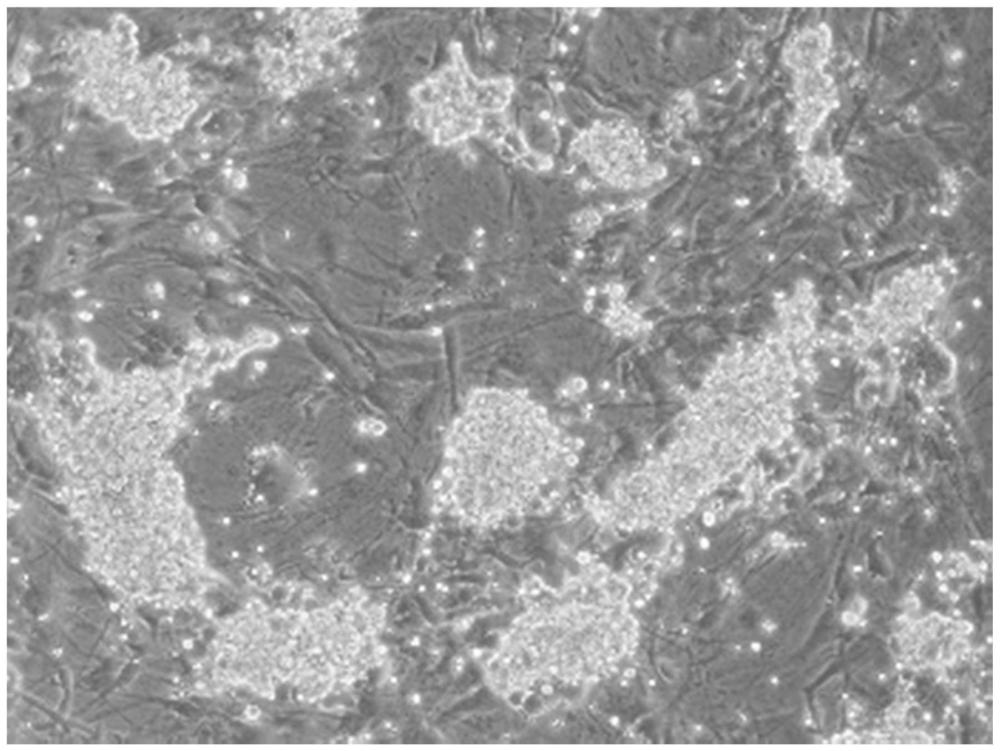

| 摘要: | 本发明属于干细胞生物学及细胞重编程领域,具体涉及EGFR抑制剂在提高精原干细胞重编程效率中的应用。本发明还提供了一种组合物,包含EGFR抑制剂、维生素C、SGC707、牛磺熊去氧胆酸;所述EGFR抑制剂为瑞香素和表没食子儿茶素没食子酸酯中的至少一种。该组合物在不导入、不使用任何外源基因/转录因子/MicroRNA(miRNA),及相关的RNA、多肽或蛋白质等诱导因子的情况下,可简便、快速、高效诱导精原干细胞重编程为具有良好的体内外分化潜能及种系嵌合能力的多能干细胞,且各组分成药性好、成本低、稳定性好、操作简单。 | ||||